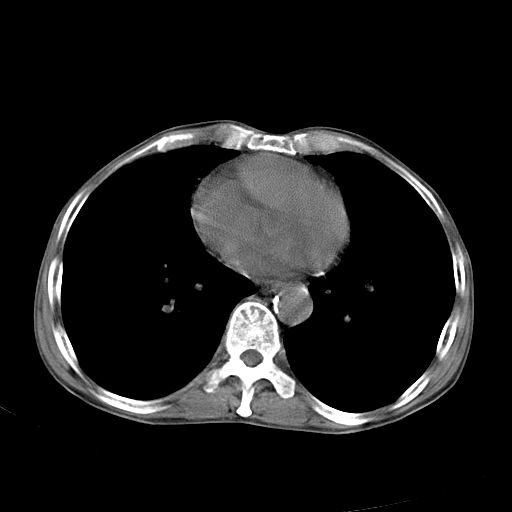

以下是引用苯小孩在2007-5-24 12:47:00的发言:[br]右侧肺门处不均匀密度软组织块影,远端肺组织见斑片模糊影,纵隔内淋巴结明显肿大,边界不清.<纵隔窗第12层面支气管内似见软组织结节>[br]考虑:1、右侧中央性肺癌并阻塞性肺炎并纵隔淋巴结转移可能性大.建议强化或纤支镜进一步检查.[br]2、隆突下淋巴结肿大/食道病变?请做鉴别检查.

以下是引用jw-830在2007-5-24 15:24:00的发言:[br][br] [br] 考虑右肺中央型肺癌并阻塞性炎症,右肺门及纵隔淋巴结转移。 [br] [br][br]